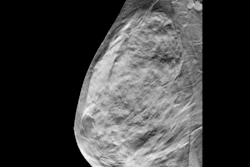

Examples of AI-only flagged findings corresponding with benign calcifications. (A to C) Synthetic views from false-positive screening DBT examinations in three different patients, including dystrophic round calcifications in 63-year-old patient (A), skin calcifications in 49-year-old patient (B), and vascular calcifications in 71-year-old patient (C). No patient was diagnosed with breast cancer within one year after screening examination.ARRS